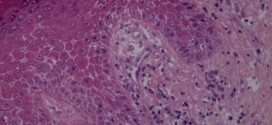

Leer MásTUMOR OVÁRICO MUCINOSO

Los tumores mucinosos están caracterizados por quistes y glándulas revestidas por células que contienen moco. Representan un 15% de los tumores ováricos. Aproximadamente un 75% son benignos, un 10% borderline; y un 15%, carcinomas. Los tumores de ovario mucinoso, representan el 15% de los tumores epiteliales de ovario, pudiendo corresponder a la estirpe serosa, mucinosa, endometrioide, células claras o células …